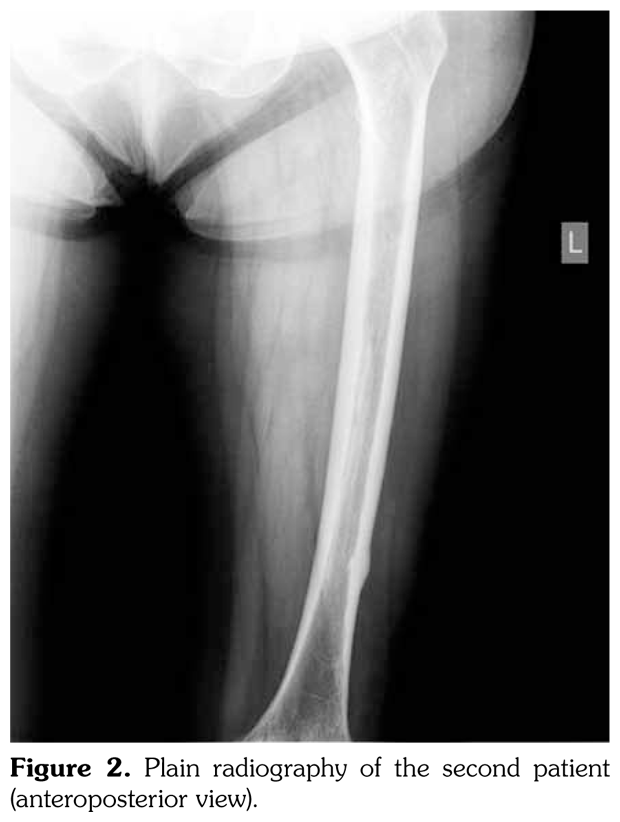

Case 2– A 61-year-old female patient presented with anterior thigh pain and difficulty in walking. Pain severity was 7 over 10 point according to visual analog scale. She had been treated with alendronate 70 mg per week with calcium plus vitamin D for two years. Plain radiographs of femur were taken upon clinical presentation. Cortical stress reaction was detected in both femoral shafts on plain radiographs (Figure 2). Computed tomographic imaging was performed to rule out fracture (Figure 3). Bone scintigraphy showed increased uptake in distal (1)/3 ends of femoral shafts (Figure 4). Serum calcium value was normal and urinary deoxypiridinoline level was mildly increased (46 nM/mMCre).

Radiologically, femoral periosteal stress reaction is described as the presence of the dreaded black line which is a transverse black line traversing the cortex that can be complete or incomplete.(6-9) Magnetic resonance imaging findings of femoral periosteal stress reaction include focal cortical thickening, bone edema, focal cortical resorption cavities and dreaded black line. There is an association between radiographic findings and the presence of clinical symptoms.(10) Similarly, our patients had thigh pain and difficulty in walking.